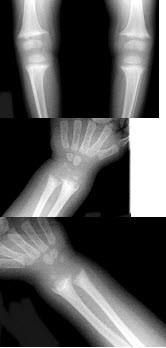

E.双足跟并拢,足尖自然外旋

女,1岁,身体发育异常,眼巩膜呈蓝色,结合图像,最可能的诊断为()

A.成骨不全